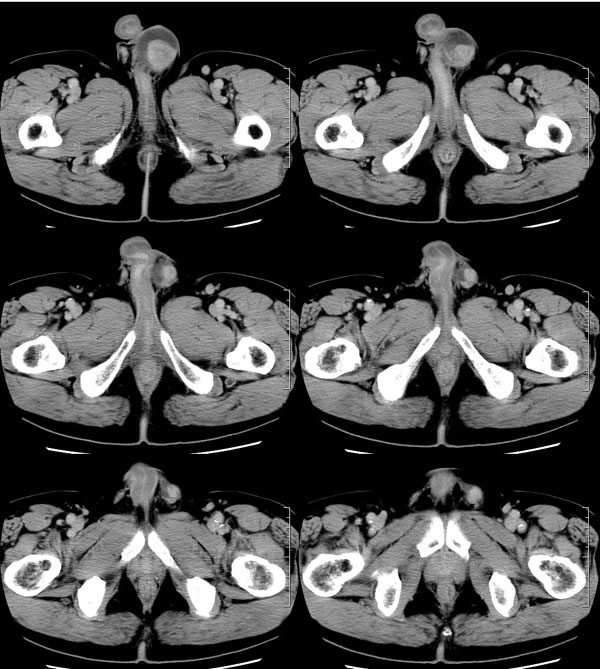

| 男性,69岁。自2个月前开始无意中发现左侧阴囊内一鸡蛋大小肿物,当时无伴疼痛等不适,未予重视。肿物逐渐增大,近段时间常伴左会阴部、腹股沟区牵扯不适,并于2周前在我院门诊行彩超检查提示“左侧附睾肿瘤可能,左侧睾丸鞘膜积液”。 专科检查:左侧阴囊肿大,其内可触及一鹅蛋大小肿物,表面光滑。肿物前部呈囊性感,后部质硬,按压无疼痛,无缩小,活动度良好。左侧睾丸未触及,透光试验(±)。                 王仕学发言:左侧睾丸见一密度不均肿块,边缘清楚,周围见水样密度影;考虑睾丸生殖细胞性肿瘤可能性大. 睾丸肿瘤占生殖系统肿瘤的3%-5%,占男性恶性肿瘤的0.5%-1.0%,其中生殖细胞性肿瘤占95%.睾丸肿瘤包括生殖细胞和非生殖细胞肿瘤两大类,前者占95%以上,后者不到5%.非生殖细胞肿瘤虽少见,但种类繁杂,主要有支持细胞、间质细胞和支持细胞-间质细胞瘤等功能性肿瘤,和间皮瘤、腺癌、横纹肌肉瘤、粘液性囊腺瘤、纤维上皮瘤、黑素神经外胚瘤、淋巴瘤等附属组织肿瘤。不同的病理类型的睾丸肿瘤发病率高峰不同,睾丸癌多发于35岁以前,精原细胞瘤发病高峰为30-35岁。精原细胞瘤约占睾丸肿瘤的60%,发病高峰在30-35岁。85%的患者睾丸有明显肿大,肿瘤局部侵犯力较低,肿瘤一般有明显界限。 手术:行“左侧附睾、睾丸、精索切除术”。 病理诊断:(左睾丸、附睾)肿物,为低分化腺癌。另送检(左精索远端)肿物,镜下亦为低分化腺癌。 免疫组化:ck(l)(++++)、cea(+++)、ca19-9(-)、psa(-)、plap(-)、p53(-)、vimentin(-)。 原贴地址:http://www.radinet.com.cn/forum_view.asp?forum_id=4&view_id=30707 |